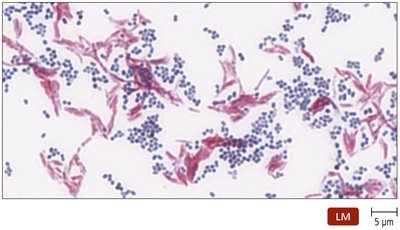

The acid-fast stain identifies bacteria with waxy cell walls, such as Mycobacterium and Nocardia. Acid-fast bacteria appear red, while non-acid-fast bacteria are blue.